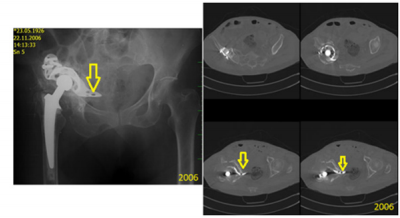

The use of bone cement is not supported in the literature. It is typically associated with early failure of the implant and no osteointegration. Our case series included several experiences of aseptic loosening. For this analysis we focused on early loosening events, which occurred as a result of insufficient fixation by screws due to bone defects or osteoporosis. The use of bone cement as a filament of bone defects, instead of bone allografts, did not produce very good results, even by firm osteosynthesis. Moreover, this technique left patients with functional ability that could only handle low load demand (Figure 7). In addition, in cases with successful allograft and achievement of good primary stability of the plate, no failure occurred when there was fracture of the plate. Primary mechanical stability of the BS plate is essential for integration of the bone allografts into defects. For pelvic disjunction, use of the BS plate as a bridging plate remains controversial because of the overall lack of patients in our series and of long-term results for those who did receive it (Figure 8).

Figure 7: Representative case of implantation of the BS plate with cement filament instead of bone allograft leading to failure within 3 years.